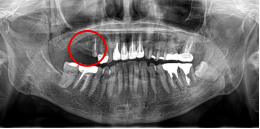

男性Nさん 70代(インプラント)

主訴

右下奥の歯が、グラグラして噛むと痛い。

治療内容

歯根の周りの骨が全く無い状態でしたので、保存することができず抜歯しました。3本歯がないところに2本インプラントを埋入しました。

所感

抜歯後、歯がなくなったところを補う方法には、部分入れ歯とインプラントがあります。この症例の場合、右下以外ほとんど歯が残っていますので、もし部分入れ歯にした場合、入れ歯のところで他のところと同じ感覚で噛むことができないので、慣れることが大変です。また部分入れ歯の支えになっている歯に負担がかかりますので、今後さらに歯を失う可能性が大きくなります。インプラントは、自分の歯と同じ感覚で噛むことができ、単独で植立していますので他の歯に負担がかかることがありませんので、更に歯を失うことを防ぎます。

インプラント2本:¥363,000✕2本=¥726,000(税込)

ポンティック1本:¥115,500(税込)

合計:¥841,500(税込)

Before

※赤丸を抜歯しました。

After